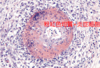

Pseudomelanosis

偽黑病變

致屍體呈現藍綠色的iron sulphide,因為:

(1) Fe in the Hemoglobin released by lysed erythrocytes reacts with

(2) H2S(硫化氫) generated by腐敗菌 (putrefactive bacteria) on the animal

* 不是因黑色素(melanin)所導致